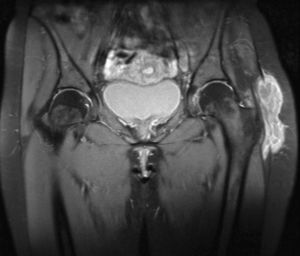

At the moment of the consultation she presented inflammatory pain in the left peritrochanteric region, which extended to the gluteus, the inguinal area and the knee, limiting movement, without a history of trauma, fever or constitutional symptoms. Examination revealed an increase in soft tissue opacity in the area, with no other inflammatory signs, as well as marked limitation to active and passive mobilization of the coxofemoral joint in all planes of movement. There was no other joint affection or respiratory problems. Laboratory testing revealed leukocytes of 13000/μl and erythrocyte sedimentation rate of 35mm in the first hour. Mantoux test was positive. A chest X-ray was normal. Imaging (Fig. 1) of the hip revealed an increase in soft tissues in the left trochanter region, with no signs of bone affection. Ultrasound and magnetic resonance of the hip revealed trochanteric bursitis. A guided aspiration of the abscess was done using ultrasound and caseum like material was obtained. Culture of this revealed the presence of Mycobacterium tuberculosis.